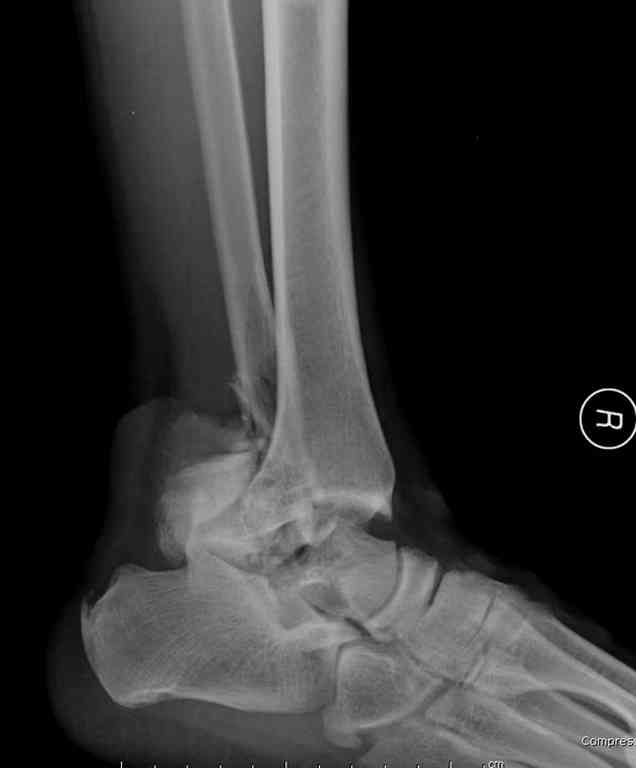

Здесь на фото примеры:

Переломовывих тарана с повреждением медиальной стороны. Через 4 часа после поступления проведена репозиция и фиксация тарана после Irrigation&Debridment. Частичное несращение медиальной лодыжки не беспокоит, вернулся к активному образу жизни. Полная нагрузка разрешена через 11 недель. Финальные снимки через 11 месяцев.